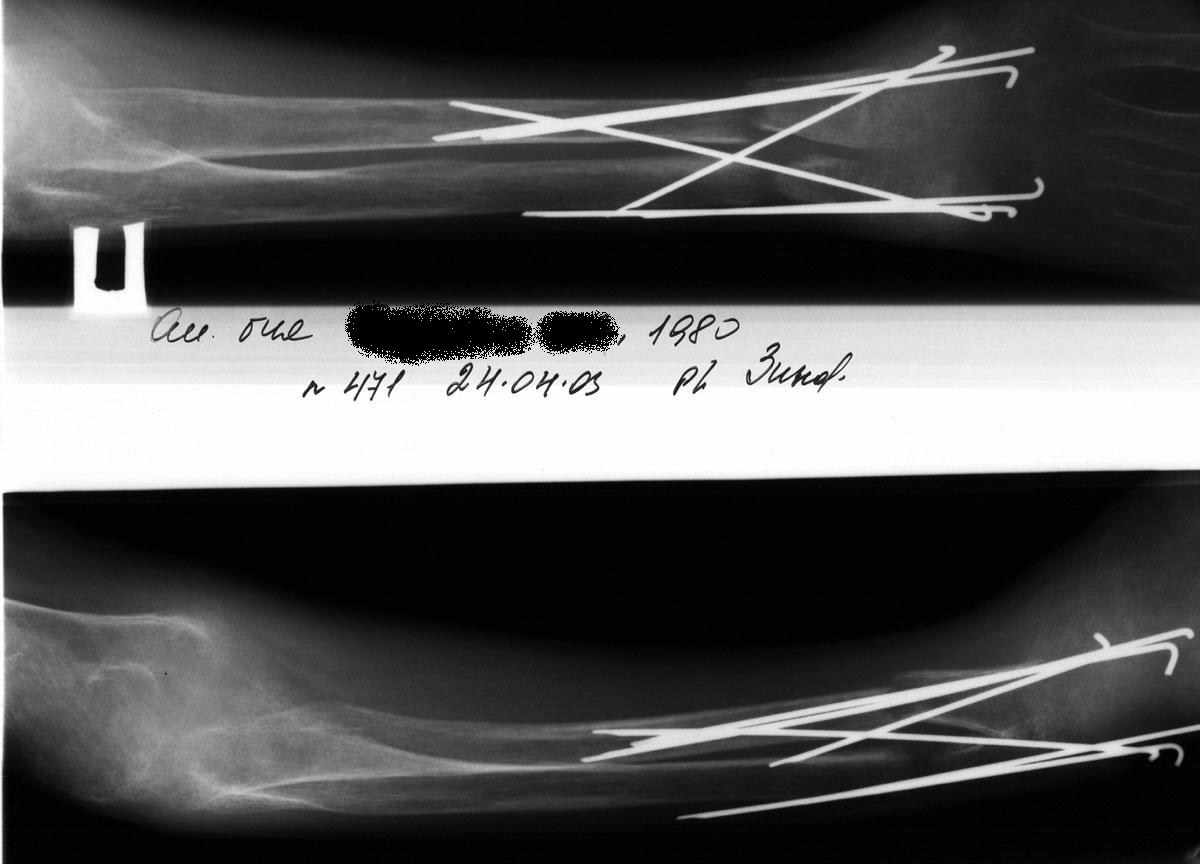

Выписка из амбулаторной карты пациента, 1980 г.р.Находится под наблюдением в поликлинике КНЦ РАН. Состоит на "Д" учёте по заболеваниям:Ювенильный идиопатический генерализованный остеопороз. Деформация грудной клетки за счёт множественных переломов грудины, рёбер. S-образный кифосколиоз грудного отдела позвоночника.Синдром гипофосфатемии неясного генеза. ВСД по кардиальному типу.Инвалид 1-й группы с детства. Последние 4 года не может передвигаться, возникают патологические переломы. Живёт в семье, материально-бытовые условия удовлетворительные.За последние 2 года состояние значительно ухудшилось - усилилась общая слабость, участились патологические переломы, которые не срастаются. Постоянно лежит в постели. Постоянный приём препаратов кальция и диеты с повышенным содержанием кальция, фосфора и белка эффекта не дают. С 11.07.2002 по 30.07.2002 г. лечился в травматологическом отделении АЦГБ с переломом костей правого предплечья со смещением. С 24.08.2002 по 08.09.2002 г. лечился в терапевтическом отделении по поводу острого бронхита с бронхоспастическим компонентом.На сегодняшний день статус. Состояние относительно удовлетворительное. В сознании. Положение вынужденное: сидя в инвалидном кресле, сам встать на ноги и передвигаться не может, туалет только с помощью родственников. Бледный, астеничный. Выраженная деформация грудной клетки, выраженный кифоз и сколиоз грудного отдела позвоночника. Экскурсия грудной клетки ограничена. Участие в акте дыхания вспомогательных межрёберных мышц. Пальпация грудной клетки безболезненна. Деформация всех крупных и мелких суставов за счёт увеличенных эпифизов. Деформация длинных трубчатых костей, мышцы рук и ног атрофичны. Температура - 36,8, ЧД - 29 в минуту. Дыхание жёсткое, проводится во все отделы. Слева от угла лопатки и в аксиллярной области влажные мелкопузырчатые хрипы, в межлопаточной области с обеих сторон свистящие хрипы. Пульс 90 ударов в минуту, ритмичный, симмитричный, слабого наполнения и напряжения. АД 120\80 мм рт. ст. Границы относительной сердечной тупости не расширены. Тоны сердца громкие, ритм правильный. Язык влажный, блестит. Живот при пальпации мягкий, не вздут, симметричный, участвует в акте дыхания, безболезненный. Печень по краю рёберной дуги. Стул регулярный, оформлен, без патологических примесей. Мочеиспускание свободное, безболезненное. Симптом Пастернацкого отрицателен с обеих сторон. Отёков нет.Анализ крови общий 26.08.2002: Hb-146 г\л, Эр.-4,8, ЦП-0,91, Лейк.-6,4, п.-4, с.-45, э.-5, м.-11, СОЭ-4 мм\ч.Анализ мочи общий 26.08.2002: Уд. вес-1025, белок-0,01, сахар-нет, лейк.-0-1 в поле зр., слизь+++, бактерии+.Анализ крови биохимический 26.08.2002: глюкоза-4,9, АЛТ-0,3, АСТ-0,5, биллирубин-11,9, креатинин-44,2, мочевина-3,8, СРБ (+).Анализ крови на микрореакцию - отрицательный.Флюрограмма за 2002: Резко выраженная деформация грудной клетки за счёт множественных переломов рёбер, грудины. Инфильтративных теней в лёгких не определяется. По сравнению с предыдущим исследованием от 01.12.2000 г. - ухудшение: нарастают деформация грудной клетки и позвоночника.ЭКГ за 2002 год: Синусовая тахикардия с ЧСС 88 в минуту. Отклонение ЭОС вправо. Признаки нарушения процессов реполяризации миокарда задней стенки левого желудочка. Повидимому, изменения ЭКГ обусловлены позиционными изменениями, возможно астеничным телосложением.Дополнительные методы исследования.Рентген правого предплечья (17.10.2002): Металлоостеосинтез по поводу перелома обеих костей правого предплечья в н\з: признаки репарации практически не определяются, сохраняется диастаз между отломками.Рентген правого предплечья (24.04.2003): Металлоостеосинтез по поводу перелома обеих костей правого предплечья в н\з: признаки репарации отсутствуют, формируются ложные суставы. Резко выраженный остеопороз.Рентген правого бедра (18.02.2003): Несросшийся перелом правого бедра на границе с\з и н\з со смещением отломков под углом открытым кнутри. Формирующийся ложный сустав. Выраженный остеопороз костей.Рентген правого бедра (24.04.2003): Угловое смещение отломков правого бедра увеличилось. Признаки репарации крайне вялые: по наружному краю отломков формируются замыкательные пластинки - ложный сустав. Выраженный остеопороз.